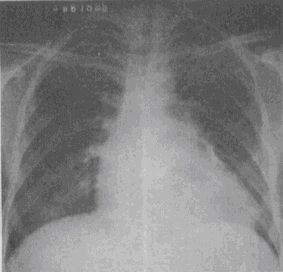

患者,男,34岁,心悸、腹胀,胸片如图,最可能的诊断是

A.心包积液

B.缩窄性心包炎

C.扩张性心肌病

D.肥厚性心肌病

E.风湿性心脏病二尖瓣狭窄

[单选题]患者,男,34岁,心悸、腹胀,胸片如图,最可能的诊断是A.心包积液B.缩窄性心包炎C.扩张性心肌病D.肥厚性心肌病E.风湿性心脏病二尖瓣狭窄

[单选题]患者,男,34岁,心悸、腹胀,胸片如图,最可能的诊断是A.心包积液B.缩窄性心包炎C.扩张性心肌病D.肥厚性心肌病E.风湿性心脏病二尖瓣狭窄

[单选题]患者,男,34岁,心悸、腹胀,胸片如图,最可能的诊断是( )。A.心包积液B.缩窄性心包炎C.扩张性心肌病D.肥厚性心肌病E.风湿性心脏病二尖瓣狭窄